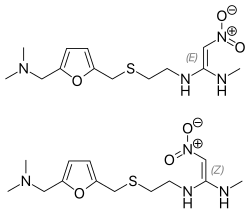

В 1975-м году появился циметидин («Smith Kline and French»), в 1979-м — ранитидин («Smith Kline and French»), в 1984-м — фамотидин («Merck»), в 1987-м — низатидин («Eli Lilly and Company», США). H2-блокаторы сразу стали «золотым стандартом» терапии кислотозависимых заболеваний, а ранитидин к 1988 году — наиболее продаваемым рецептурным препаратом и оставались ими до появления ингибиторов протонного насоса (омепразола).

Ранитидин имеет меньше типичных для циметидина побочных эффектов, а препараты последующих поколений — ещё меньше. При этом активность фамотидина в 20—60 раз превышает активность циметидина и в 3-20 раз активность ранитидина. По сравнению с ранитидином фамотидин более эффективно повышает pH и снижает объем желудочного содержимого. Длительность антисекреторного действия ранитидина — 8-10 часов, а фамотидина — 12 часов[1].